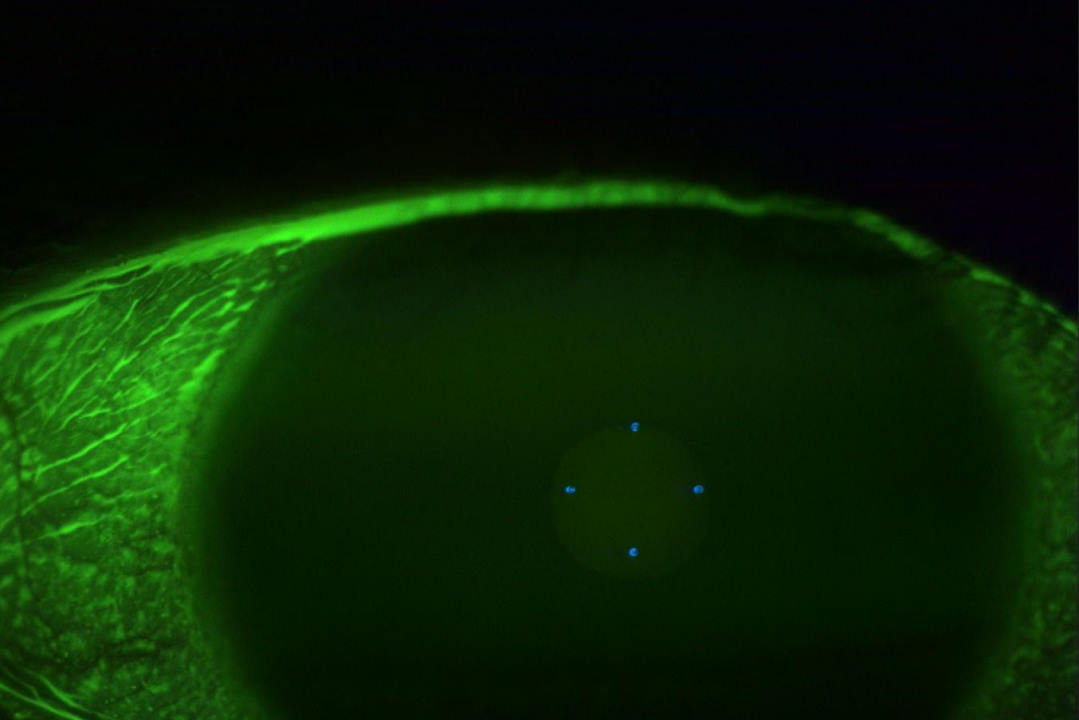

Examination revealed visual acuity of 6/9 in the affected eye, with OCT confirming persistent subretinal fluid. Autofluorescence imaging showed only minimal scarring from previous laser treatment with no evidence of RPE atrophy at the fovea. OCT-angiography ruled out secondary choroidal neovascularisation.

The treatment protocol involved threshold laser photocoagulation to the previously treated distant leak where minimal scarring suggested room for additional treatment, combined with subthreshold laser photocoagulation applied to the entire area of subretinal fluid, including both leak sites. The subthreshold approach was particularly crucial for the juxtafoveal leak, where conventional threshold treatment would carry unacceptable risks.

Subthreshold laser represents a paradigm shift in retinal photocoagulation. Rather than creating visible tissue damage, it delivers energy below the threshold for observable retinal changes, using duty cycle modulation to release energy in short pulses that allow tissue cooling between each pulse.

This approach enables selective RPE targeting while preserving overlying photoreceptors. In CSCR, therapeutic benefits likely stem from enhanced RPE metabolic activity and fluid transport capacity, restoration of tight junction integrity and modulation of growth factor expression through heat shock protein pathways.

The results were notable from an anatomical standpoint. At two-month follow-up, OCT demonstrated complete resolution of subretinal fluid, while autofluorescence imaging confirmed preservation of RPE integrity at the fovea with no treatment-related damage.